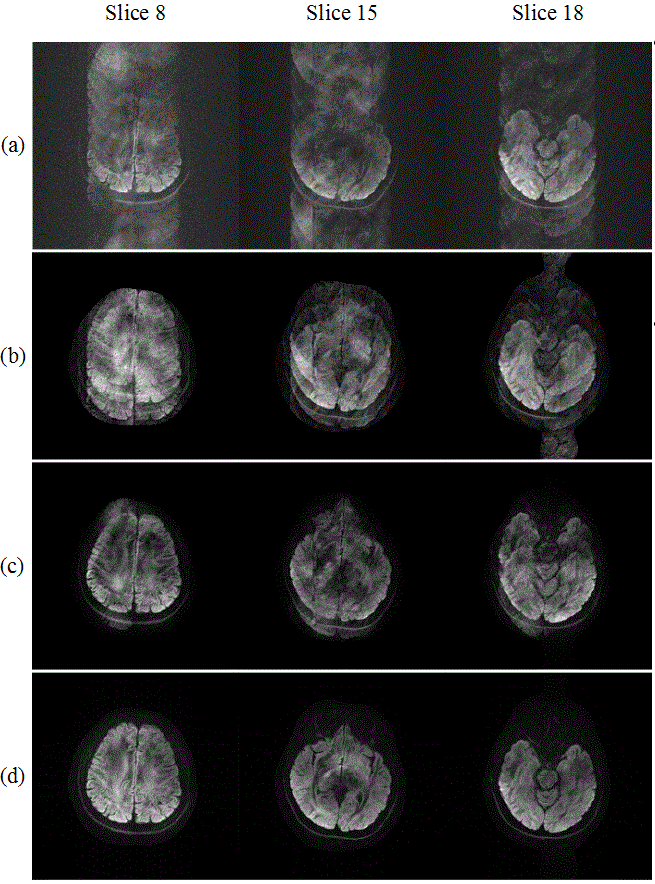

图2. 十二次激发扩散加权图像重建结果。(a)直接重建(b)POCS-ICE重建结果(c)POCS-MUSSELS重建结果(d)所提方法重建结果。

该方法利用磁共振图像的相位光滑特性构造Hankel矩阵,并通过引入约束矩阵部分奇异值和的方式来约束Hankel矩阵的低秩特性。该方法的重建结果比其它前沿方法的重建图像具有更少的伪影,尤其在激发数较大时的优势更加明显。另外,该方法对预估的Hankel矩阵的秩数不敏感,在秩数设置在一定范围内时,都有较好的重建结果。